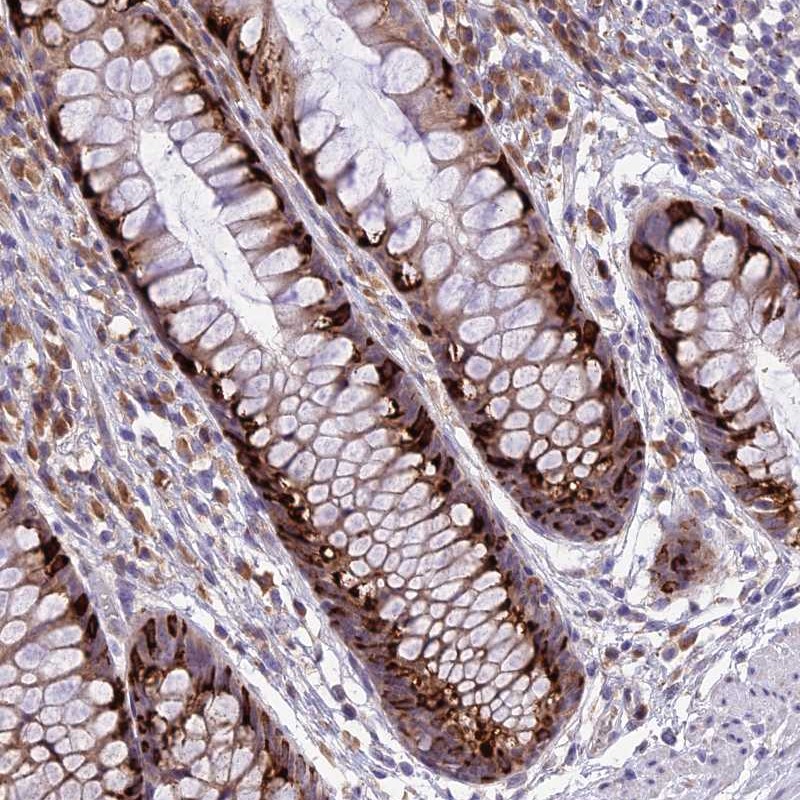

Immunohistochemical staining of human rectum shows strong cytoplasmic positivity in goblet cells.